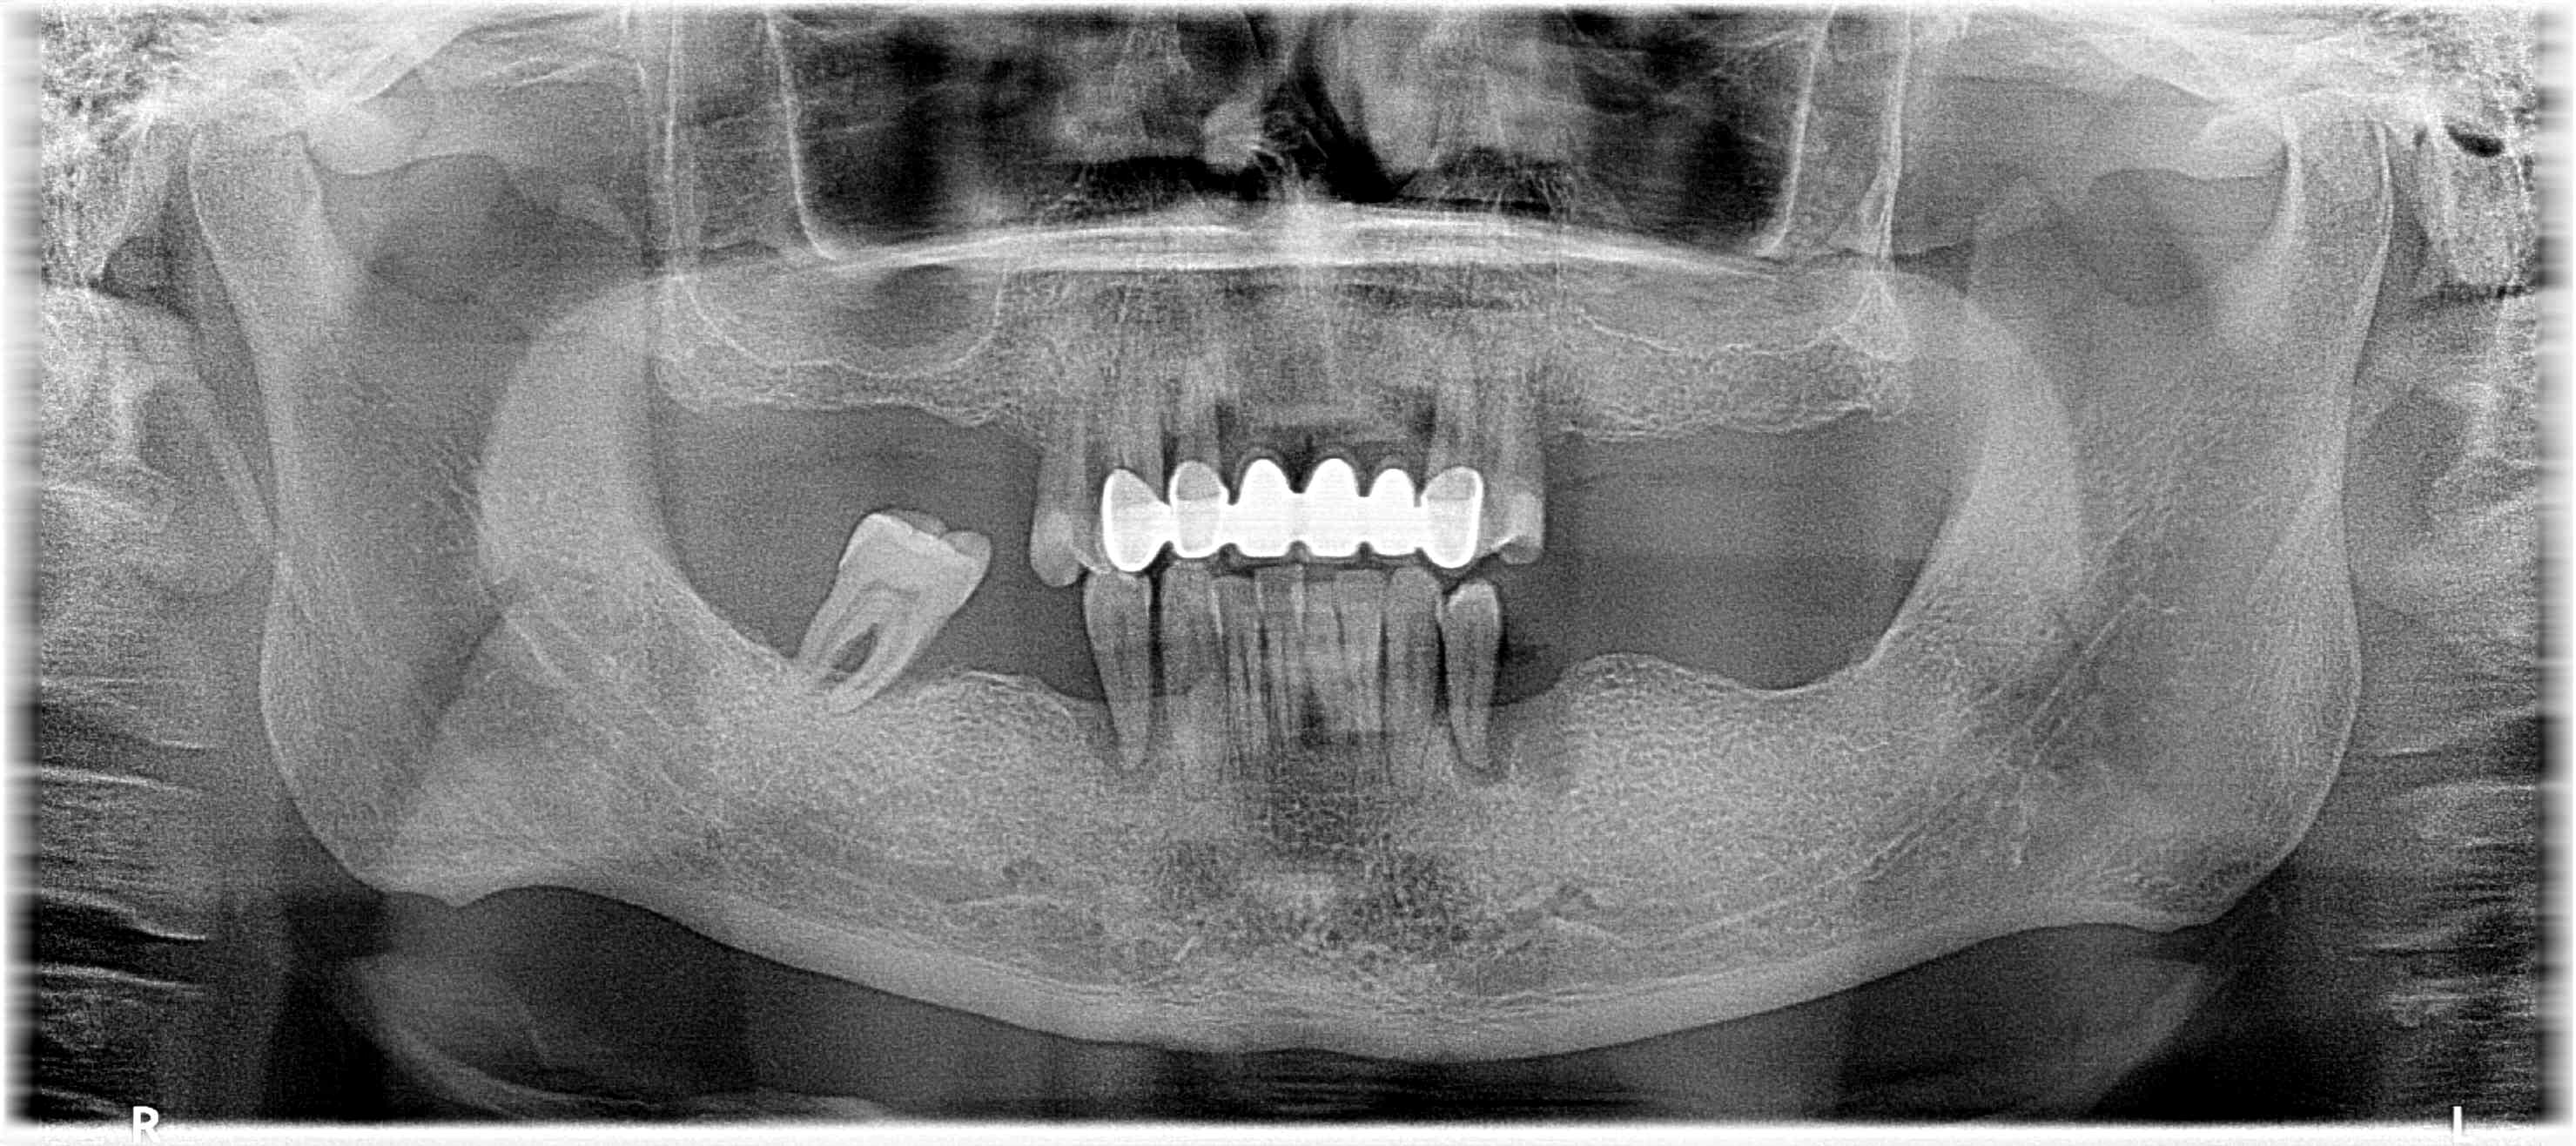

MAPA Health Care in Turkey, Istambul: 8 Implantate und ALL-on 4 im Ober- und Unterkiefer

• inklusive Interimsversorgung: OK und UK

• alle vorhandenen ZĂ€hne mĂŒssen entfernt werden

• HKP aus TĂŒrkei